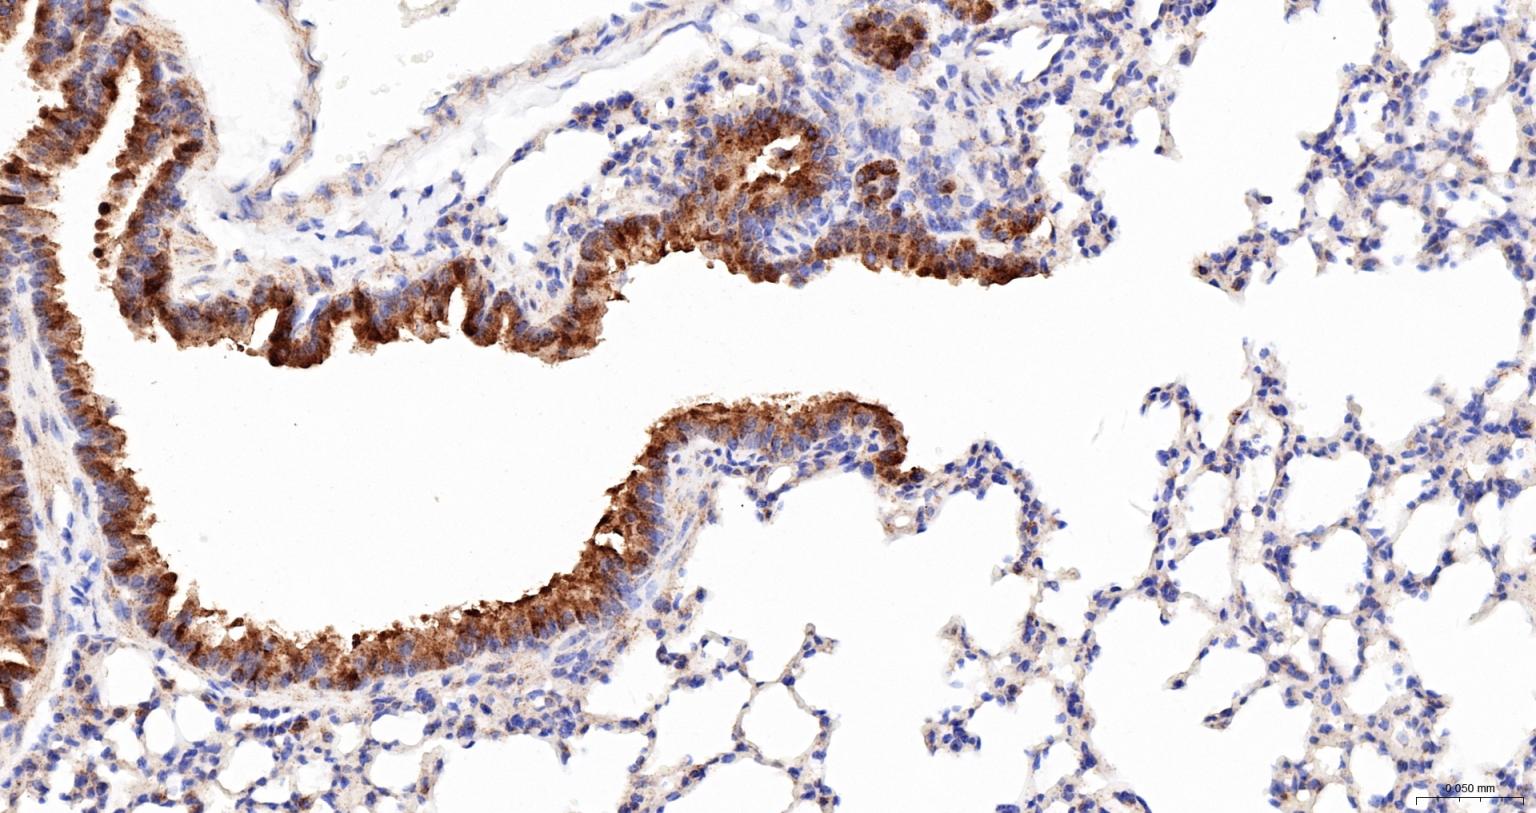

Paraformaldehyde-fixed, paraffin embedded Mouse Lung; Antigen retrieval by boiling in sodium citrate buffer (pH6.0) for 15 min; The section was incubated with HSP105 Monoclonal Antibody, Unconjugated (bsm-61340R) at 1:200 overnight at 4°C, followed by conjugation to the bs-0295G-HRP and DAB (C-0010) staining.

Paraformaldehyde-fixed, paraffin embedded Human Lung; Antigen retrieval by boiling in sodium citrate buffer (pH6.0) for 15 min; The section was incubated with HSP105 Monoclonal Antibody, Unconjugated (bsm-61340R) at 1:200 overnight at 4°C, followed by conjugation to the bs-0295G-HRP and DAB (C-0010) staining.

Paraformaldehyde-fixed, paraffin embedded Rat Lung; Antigen retrieval by boiling in sodium citrate buffer (pH6.0) for 15 min; The section was incubated with HSP105 Monoclonal Antibody, Unconjugated (bsm-61340R) at 1:200 overnight at 4°C, followed by conjugation to the bs-0295G-HRP and DAB (C-0010) staining.